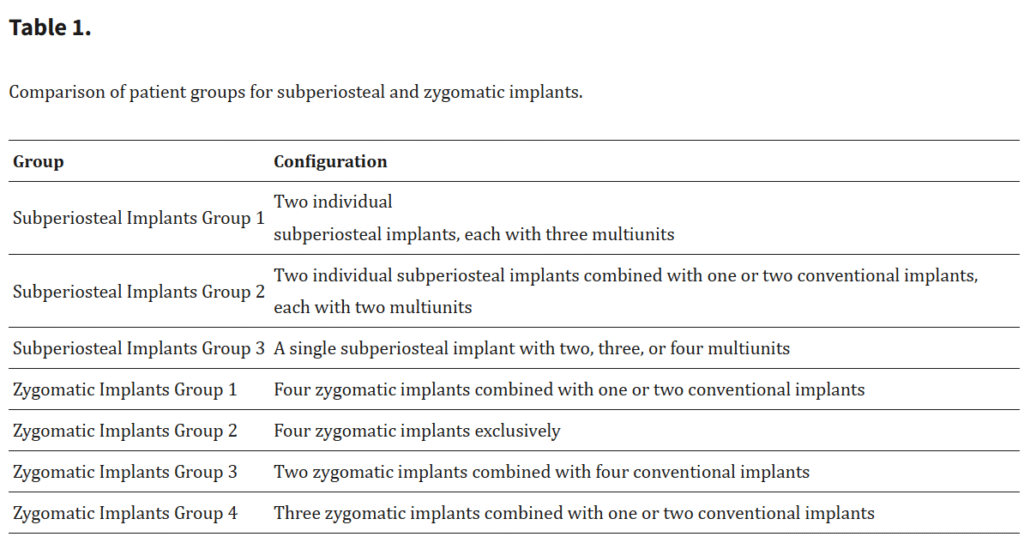

研究対象は、治療に用いられたインプラントの種類および構成に基づき、明確に区分されたグループに分けられた(Table 1)。

サブペリオステアルインプラント群

89名の患者が、インプラントの構成に応じて3つのサブグループに分類された:

グループ1:51名 ― 各3本のマルチユニットを備えた2つの個別骨膜下インプラントで治療

グループ2:24名 ― 各2本のマルチユニットを備えた2つの個別骨膜下インプラントと、1~2本の従来型インプラントを併用

グループ3:14名 ― 2~4本のマルチユニットを備えた単一の骨膜下インプラントで治療

ザイゴマインプラント群

81名の患者が、インプラントの本数と配置に基づいて4つのグループに分類された:

グループ1:14名 ― 4本のザイゴマインプラントと1~2本の従来型インプラントを併用

グループ2:15名 ― 4本のザイゴマインプラントのみで治療

グループ3:46名 ― 2本のザイゴマインプラントと4本の従来型インプラントを併用

グループ4:6名 ― 3本のザイゴマインプラントと1~2本の従来型インプラントを併用

このような詳細な分類により、インプラント構成とその治療結果を精緻に分析することが可能となった。骨膜下インプラント群とザイゴマインプラント群の各グループは、それぞれ特有の特徴と治療プロトコールを有しており、比較評価における強固な基盤を提供した。